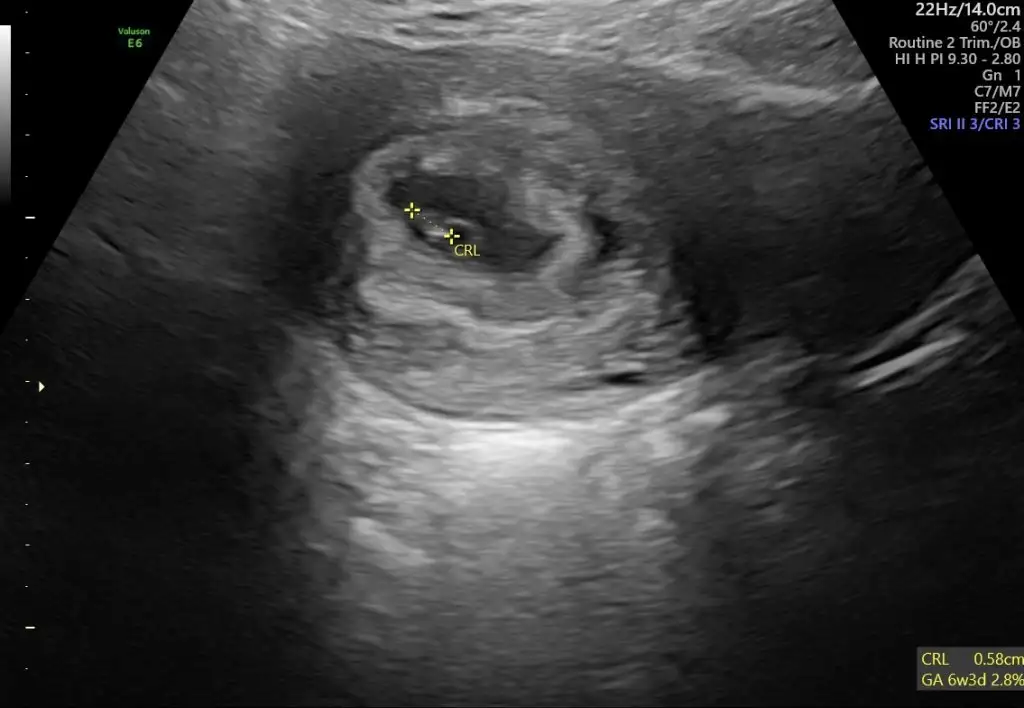

Bende merak ediyorum 6 haftalık karından çekildi 🥰

Eklentiler

• IMG_20230706_155308.webp

IMG_20230706_155308.webp

26,1 KB · Görüntüleme: 98